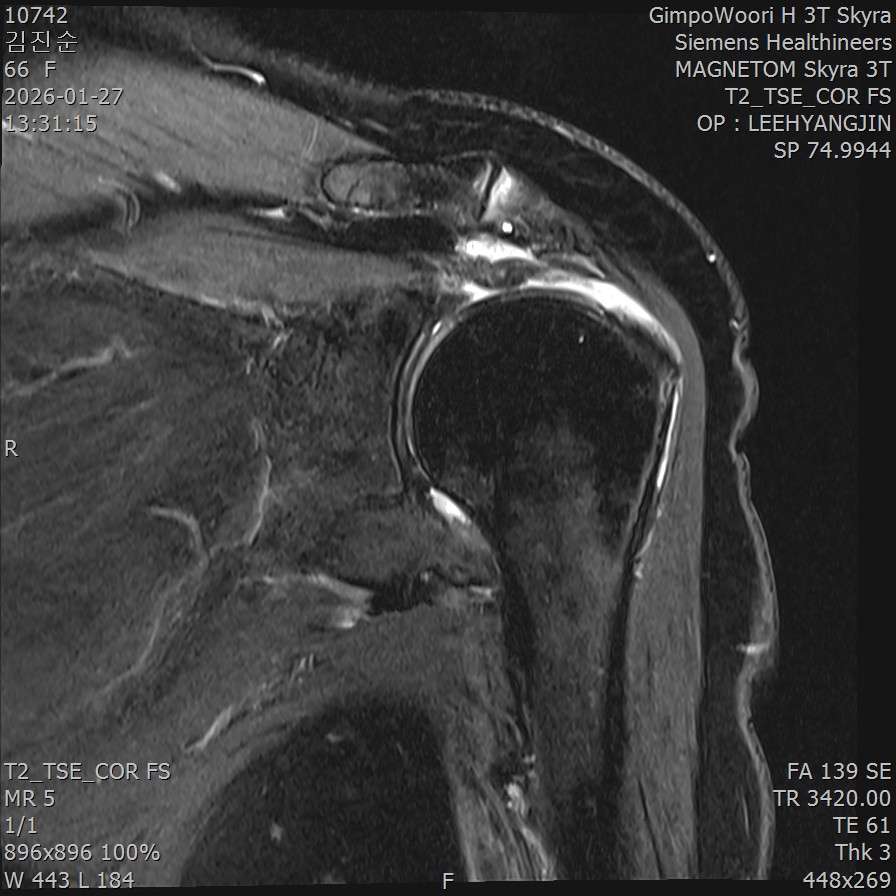

MRI 영상에서는 큰 이상이 보이지 않았습니다. 그런데 초음파로 어깨를 움직이면서 검사하니, 회전근개가 결대로 세로로 찢어진 형태의 파열이 확인되었습니다. 팔을 움직일 때마다 찢어진 인대 섬유가 갈래갈래 벌어지면서 통증과 염증을 유발하고 있었던 것입니다.

MRI 검사: 관절 내부까지 봅니다

- ✓회전근개 파열의 정확한 범위

- ✓완전파열 시 인대의 퇴축(말려 들어간) 정도

- ✓관절 내부의 문제 (관절와순 손상)

- ✓어깨 연골 상태

MRI의 한계: MRI는 환자가 가만히 누워서 팔을 움직이지 않은 상태에서 촬영합니다. 따라서 움직일 때만 발생하는 문제는 놓칠 수 있습니다.

Q9. MRI에서 정상이라고 했는데 왜 아픈 건가요?

A. MRI는 정지 상태에서 촬영하기 때문에, 움직일 때만 발생하는 문제는 놓칠 수 있습니다.